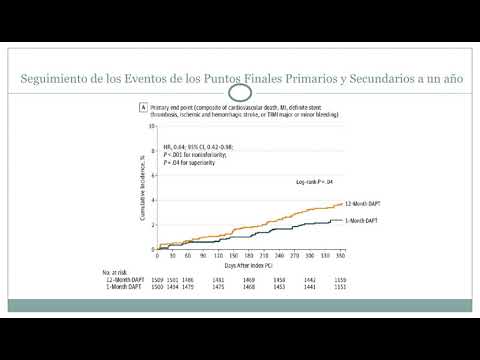

Ensayo clínico randomizado STOPDAPT-2. Dra. Jessica Volpato. Residencia de Cardiología. Hospital C. Argerich. Buenos Aires